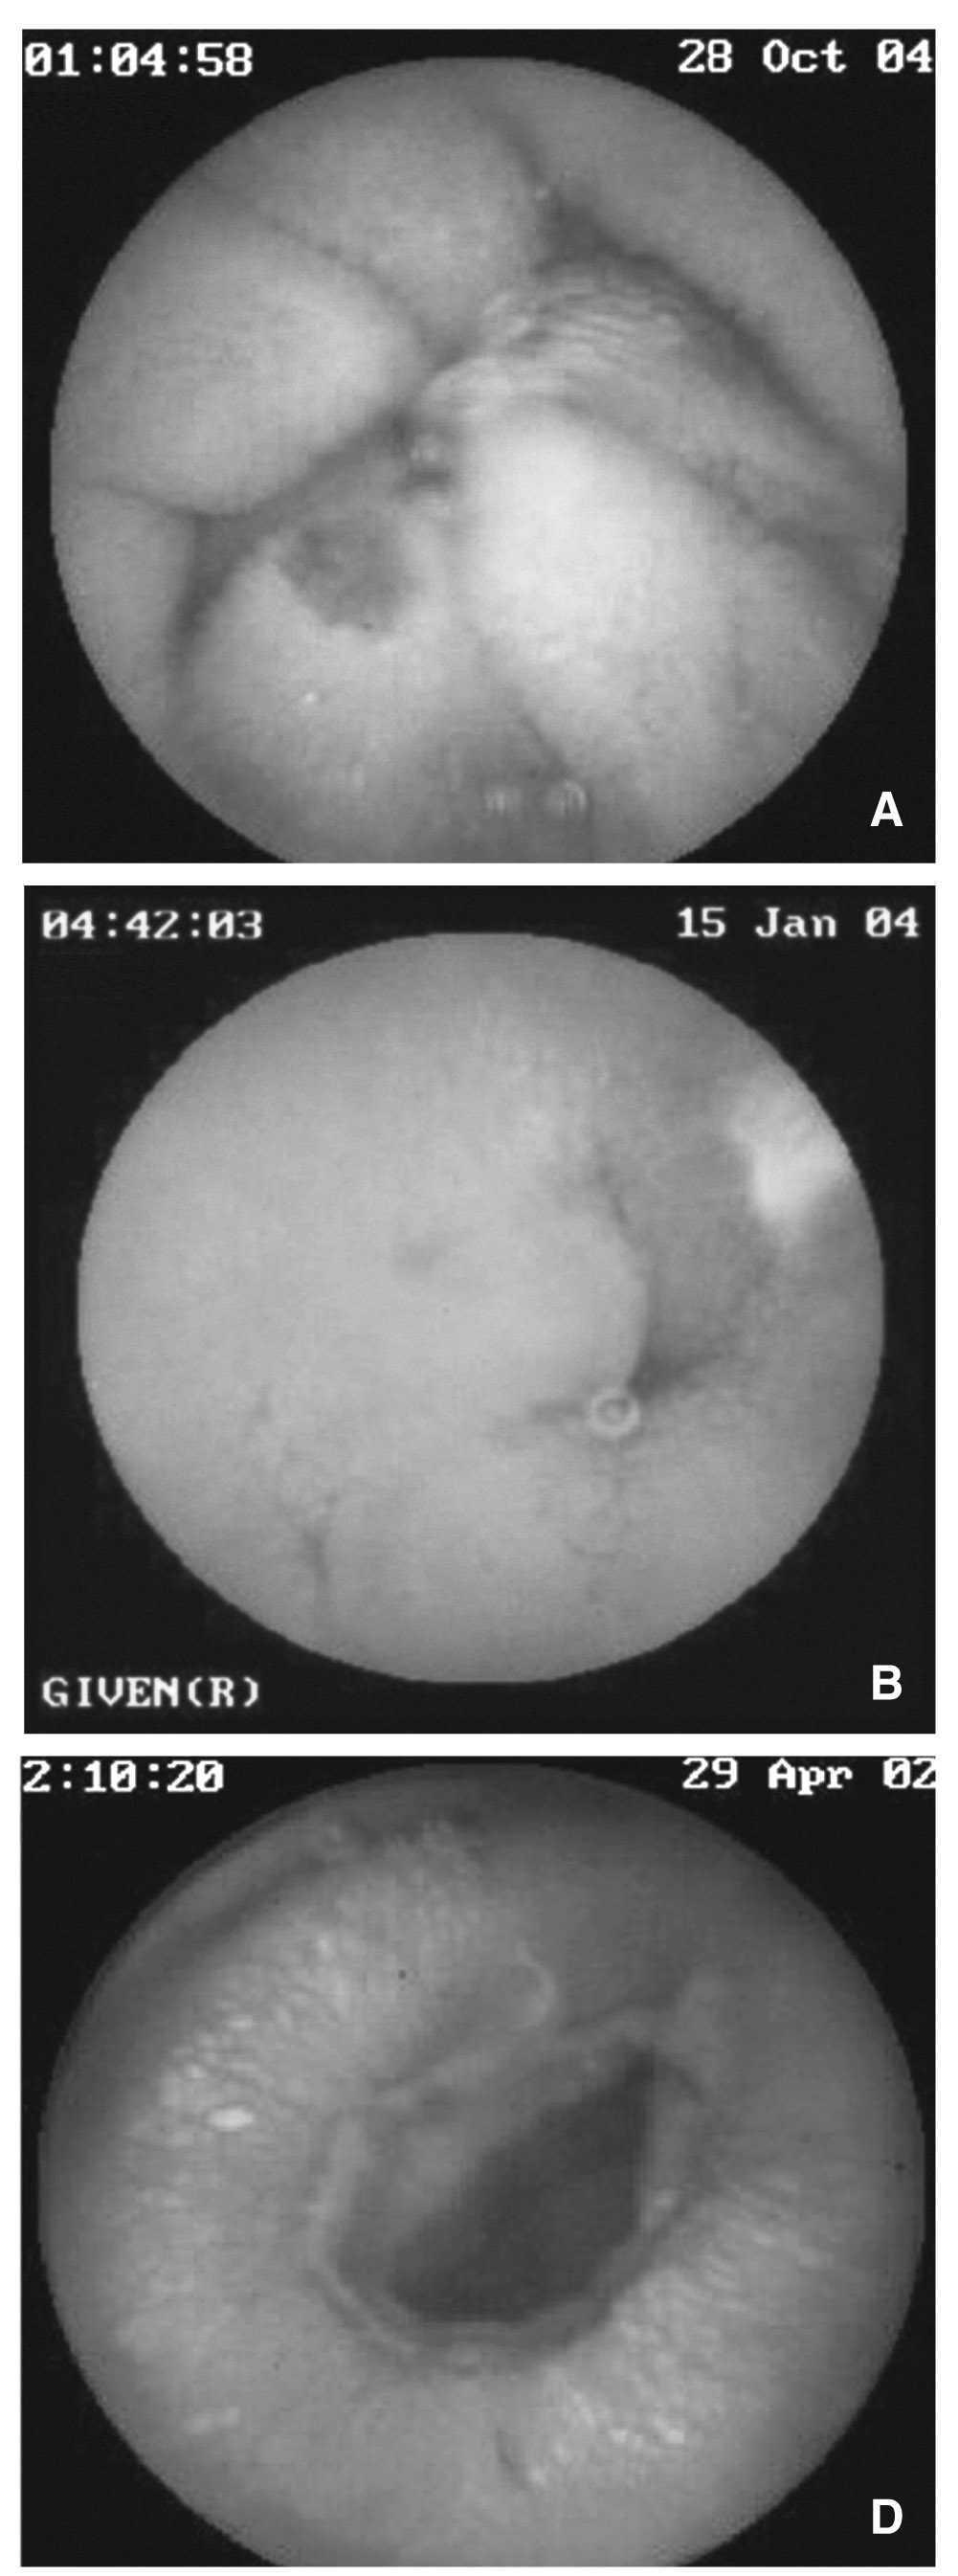

En la actualidad existen múltiples estudios comparativos de cápsula con las técnicas diagnósticas de que disponíamos hasta el momento en las diferentes enfermedades (fig. 4). A continuación analizaremos cada una de ellas de manera individualizada:

Fig. 4. Imágenes de cápsula endoscópica: a) angiodisplasia yeyunal; b) úlcera ileal; c) úlcera ileal secundaria a consumo de antiinflamatorios no esteroideos; d) úlcera circunferencial ileal estenótica; e) sangrado activo de úlcera duodenal.